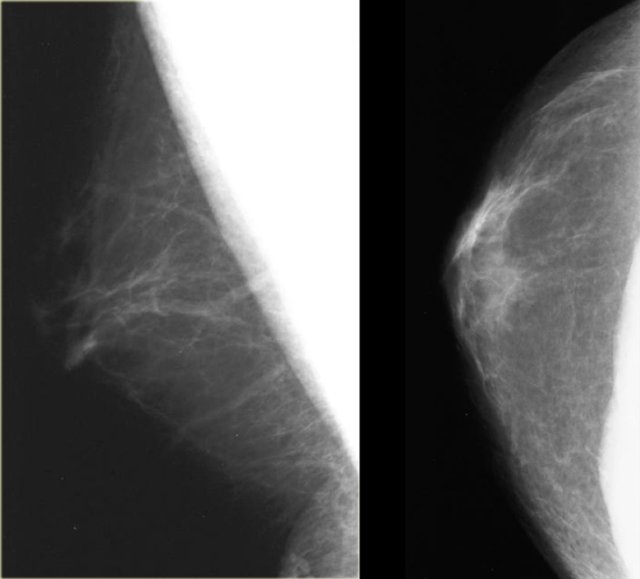

On the left two examples of a normal male mammogram.

The left image shows normal skin, a nipple and a small amount of connective tissue behind the nipple.

The image on the right shows a bit more connective tissue, but this is still normal.

Normal male mammogram Normal male mammogram

On the left another normal male breast.

There is more fatty tissue and there are a number of blood vessels.

There is a small amount of fibrous connective tissue, but basically most of this breast is just fat.